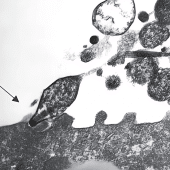

Российские ученые оценили влияние сопутствующих вирусных инфекций у детей с пневмонией, вызванной Mycoplasma pneumoniae, а также определили, существуют ли различия в устойчивости к антибиотикам у пациентов из Европейской России и Дальнего Востока. В результате исследования у 62% пациентов выявлены сопутствующие вирусные инфекции. Уровень резистентности к антибиотикам составил 40%, что выше, чем в европейских странах, но значительно ниже, чем у пациентов из Азии.